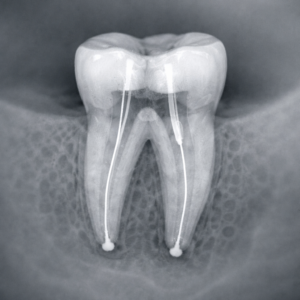

Endodoncia Multiradicular

Tratamiento de conductos en muelas con varias raíces que permite eliminar la infección del interior del diente, aliviar el dolor y conservar la pieza dental, evitando su extracción.